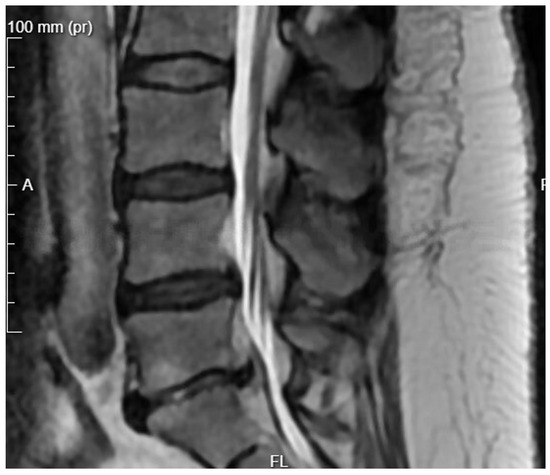

Patient Background: A 50-year-old female patient with a body mass index (BMI) of 32 was admitted to the neurology emergency department due to an acute spinal pain syndrome persisting for three days. The pain, VAS 7, was located in the lower spine, radiating bilaterally to both lower limbs, and exacerbated by movement. The patient had undergone a gynecological procedure under epidural anesthesia one month prior to this episode. Initial MRI (Figure 2) of the spine revealed a collapse of the L5/S1 space with a small central protrusion. The disc signal raised suspicion of early inflammatory changes in the eyes of the consulting neurosurgeon, though the radiologist conclusively denied inflammatory features. The patient presented with slightly elevated inflammatory markers, with a CRP level of 20 mg/L.

Diagnostic Evolution: After a week of conservative treatment without improvement, a follow-up MRI was ordered(Figure 3), which unambiguously identified spondylodiscitis with an abscess in the canal, causing compression of the dural sac and both S1 nerves (Figure 4). The patient’s pain syndrome worsened significantly, VAS 9 in the lower spine, leading to her qualification for surgical treatment.

Figure 3. Pre-operative T2 sagittal MRI image at the L5/S1 level on the day of the patient’s admission to the neurology department.